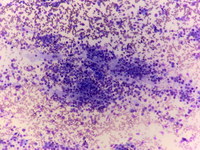

2 year old girl was evaluated for decreased energy and limping gait. Abdominal ultrasound revealed a left kidney mass.

Bone marrowexamination shows numerous clumps of metastatic tumor as well as neuropile. Vacuolization in the tumor cells is noted as well as rosetting. These findings are consistent with stage IV neuroblastoma.